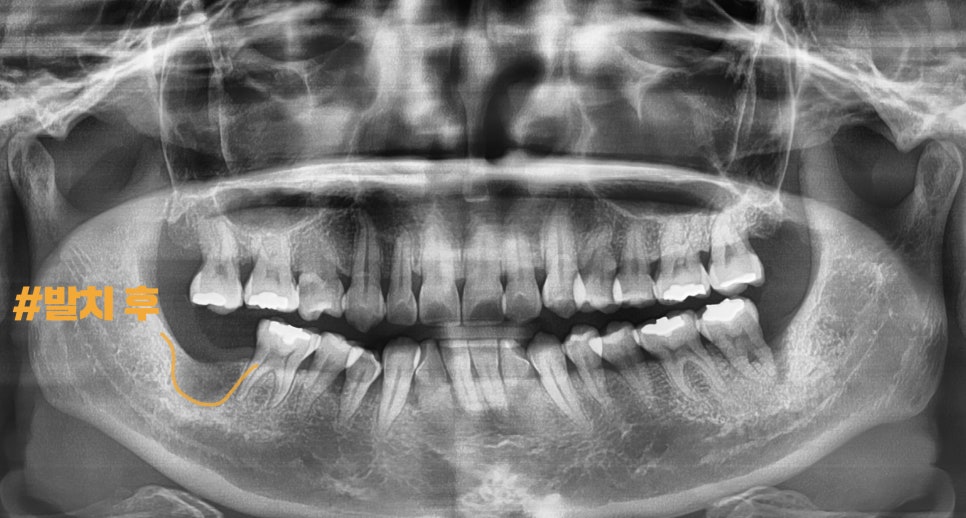

#47번 발치 후

파노라마 엑스레이를 촬영했으며

가이드라는 보조장치로,

계획된 부위에 픽스쳐를 식립할 수 있었습니다.